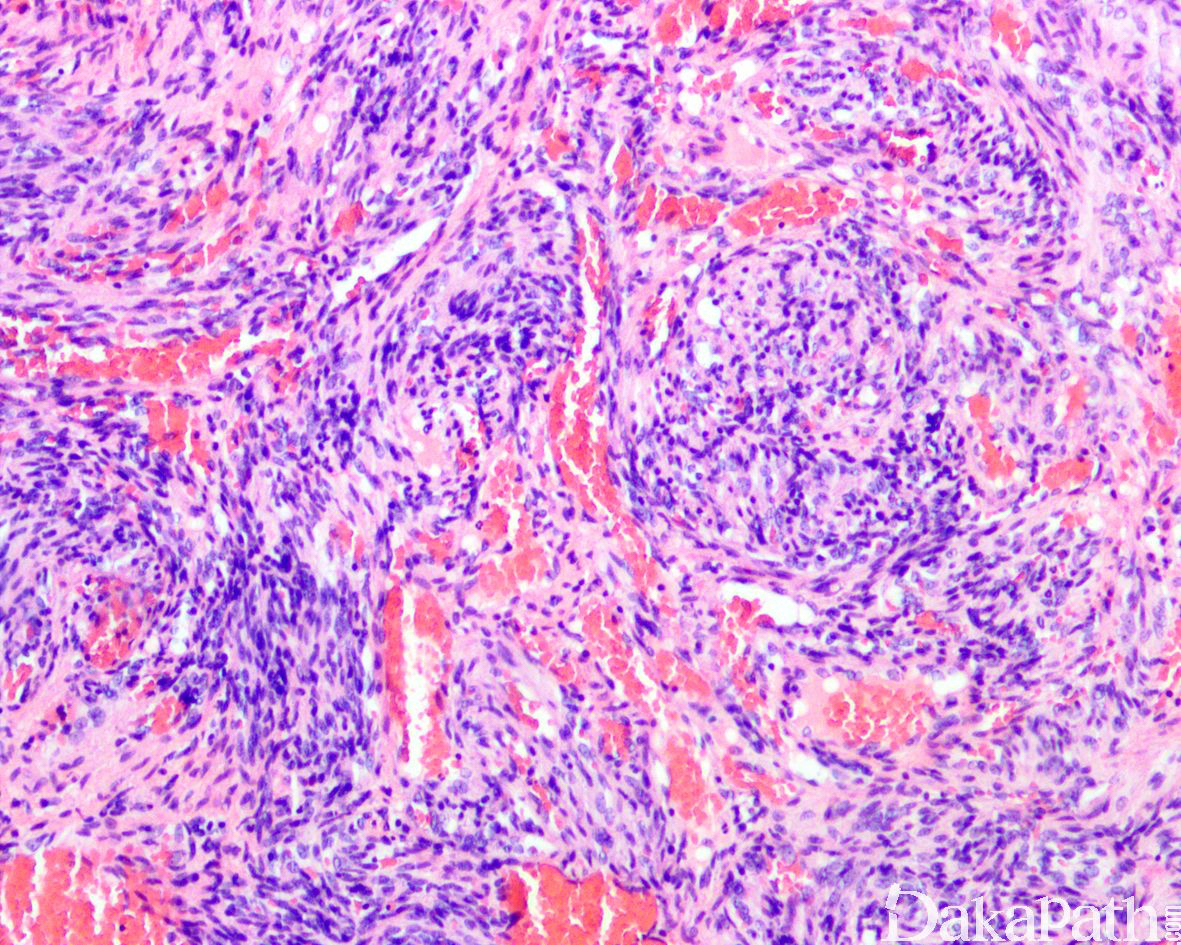

病变直径较小,通常< 2cm, 位于真皮或皮下,偶尔可位于深部软组织,组织学呈多结节状生长,主要由海绵状血管瘤样区域和实性梭形细胞区域两种成分组成,梭形细胞成分达 50%以上;

实性区域梭形细胞多和海绵状血管瘤样区域相互交融,梭形细胞呈短束状排列,其中血管或为扩张的薄壁血管,或呈不规则裂隙样,间质内常可见外渗的红细胞,类似卡波西肉瘤;

除梭形细胞外,实性区域内还可见小簇分布的圆形空泡状细胞,形态与上皮样血管内皮瘤中的空泡状细胞相似,似形成原始性脉管腔,当空泡状细胞数量较多时可类似于脂肪母细胞;瘤细胞核温和,少数可见退变的核非典型性,核分裂象罕见(< 1/50HPF);

约 50%的梭形细胞血管瘤可见肿瘤于血管内生长,10-20%的梭形细胞血管瘤可完全位于血管内。取决于血管瘤样成分和梭形细胞成分的比例多少,梭形细胞血管瘤在低倍镜下可能类似于海绵状血管瘤或 Kaposi 血管肉瘤;